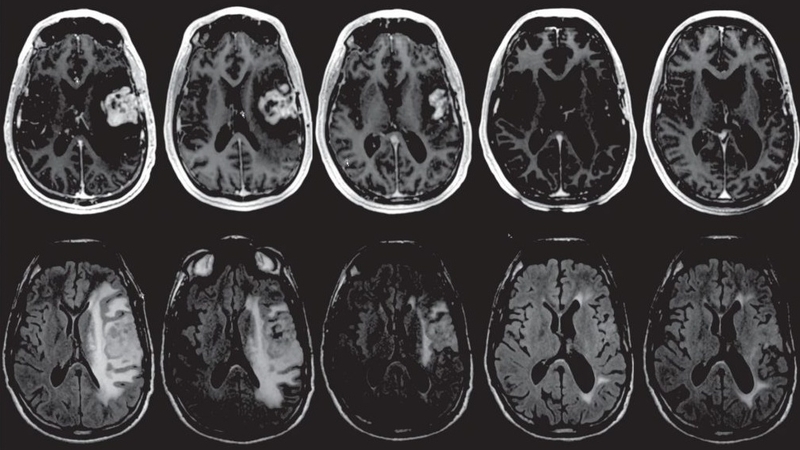

U tuyến thượng thận là bệnh hiếm gặp, các khối u phát triển trong tuyến thượng thận, có thể gây các biến chứng làm ảnh hưởng nghiêm trọng đến sức khỏe người bệnh. KU tuyến thượng thận lành tính hay ác tính cũng là một bệnh lý cần lưu tâm. Tùy thuộc vào loại u mà triệu chứng và tiên lượng có thể khác nhau.

Khối u tuyến thượng thận bắt đầu khi các tế bào khỏe mạnh trải qua sự biến đổi và tăng trưởng ngoài sự kiểm soát, hình thành thành một khối u. Khối u ung thư tuyến thượng thận là một khối u ác tính và có khả năng phát triển và lan rộng sang các bộ phận khác của cơ thể. Trái lại, một khối u lành tính có thể phát triển nhưng không lan rộng.

Khối u tuyến thận nguyên phát bắt đầu trong tuyến thượng thận và có thể là kết quả của một bệnh ung thư bắt đầu ở một cơ quan khác, chẳng hạn như phổi và sau đó lan rộng đến tuyến thượng thận qua quá trình gọi là di căn.